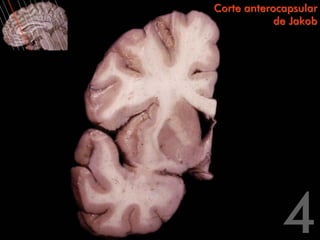

Corte anterocapsular

de Jakob

Circunvolución frontal superior   Corte anterocapsular

Surco frontal                                 de Jakob

superior

Circunvolución

frontal medial

Circunvolución frontal media

Surco del cíngulo

Surco frontal inferior

Circunvolución del

Circunvolución frontal inferior                                            cíngulo

Lóbulo de la ínsula                                                        Tronco del cuerpo

calloso

Surco lateral

temporal superior                                                   Centro oval del lóbulo frontal

Surco temporal

temporal media                                                 Circunvolución

parahipocampal

temporal inferior

Cabeza del núcleo

caudado

Brazo anterior de la

cápsula interna                               Tronco del cuerpo calloso

Asta frontal del

Cápsula externa                               ventrículo lateral

Septum pellucidum

Claustro

Pico del cuerpo calloso

Núcleo accumbens

Quiasma óptico

Cápsula extrema

Sustancia

perforada anterior

Putamen

Circunvolución frontal superior Corte anterocapsular Surco frontal de Jakob superior Circunvolución frontal medial Circunvolución frontal media Surco del cíngulo Surco frontal inferior Circunvolución del Circunvolución frontal inferior cíngulo Lóbulo de la ínsula Tronco del cuerpo calloso Surco lateral Circunvolución temporal superior Centro oval del lóbulo frontal Surco temporal superior Circunvolución temporal media Circunvolución parahipocampal Circunvolución temporal inferior

Corte anterocapsular de Jakob Cabeza del núcleo caudado Brazo anterior de la cápsula interna Tronco del cuerpo calloso Asta frontal del Cápsula externa ventrículo lateral Septum pellucidum Claustro Pico del cuerpo calloso Núcleo accumbens Quiasma óptico Cápsula extrema Sustancia perforada anterior Putamen